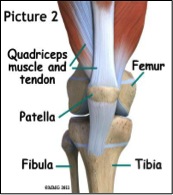

Η επιγονατίδα, το μεγαλύτερο σησαμοειδές οστό στο ανθρώπινο σώμα, τοπογραφικά βρίσκεται στην πρόσθια επιφάνεια του γόνατος, ανάμεσα στον τένοντα του τετρακεφάλου (quadriceps tendon) και τον επιγονατιδικό (patellar tendon) τένοντα (εικ. 1 και 2) και κινείται πάνω στο πιο χαμηλό άκρο του μηριαίου οστού, παίζοντας το ρόλο της τροχαλίας.

Η επιγονατίδα δρα σαν οδηγός για τον εκτατικό μηχανισμό του γόνατος, αυξάνοντας το μοχλοβραχίονα δύναμης του τετρακεφάλου και επιτρέπει την καλύτερη κατανομή της πίεσης, που ασκείται πάνω στο μηριαίο οστό, μεγαλώνοντας την επιφάνεια επαφής του επιγονατιδικού τένοντα με το μηριαίο οστό.

Η αρθρική επιφάνεια της επιγονατίδος αποτελείται από 7 αρθρικές επιφάνειες (facets), τρείς στην έσω επιφάνεια, τρεις στην έξω και μία επιπλέον στην έσω (odd facet).

O έσω καθεκτικός σύνδεσμος με τον λοξό έσω πλατύ μυ σταθεροποιούν την εσωτερική επιφάνεια της επιγονατίδας, ενώ ο έξω καθεκτικός με τον έξω πλατύ και την λαγονοκνημιαία ταινία σταθεροποιούν την εξωτερική της επιφάνεια (εικ. 3).

Επειδή όμως, η επιγονατίδα δεν βρίσκεται εντελώς σε επαφή με την αύλακά της κατά τη διάρκεια των πρώτων 0-30 μοιρών (εικ. 1) κάμψης, η αστάθεια και η πιθανότητα για τραυματισμό αυξάνεται , σε περίπτωση που οι σταθεροποιητές (μυες και σύνδεσμοι) της είναι αδύναμοι ή σε κακή ευθυγράμμιση.